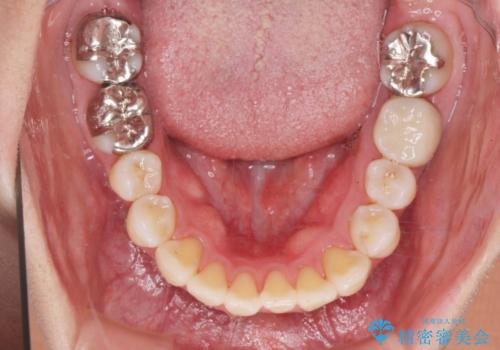

捻れた奥歯 突き出た前歯を治したい

- 出っ歯に見える前歯、捻れてしまった小臼歯の改善を求めて来院されました。

マウスピースでは改善の難しい小臼歯のねじれをまず部分ワイヤー矯正で改善し、その後マウスピース矯正で前歯の突出感を改善します。

時間はかかりましたが、捻れ、かみ合わせ、前歯の角度の改善が達成され満足いただくことができました。